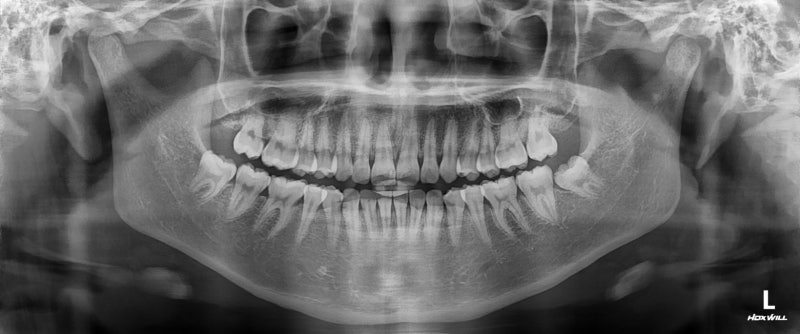

놀라운 사실은 치아를 잇몸과 턱뼈에 고정시키는 치주인대까지 이완시킨다는 것입니다. 실제로 임신 중 "치아가 흔들린다"고 호소하는 여성들이 있고, X-ray 검사로도 치아의 위치 변화가 확인된 사례들이 보고되고 있어요.

첨부 이미지

이는 일시적인 현상으로, 출산 후 릴렉신 수치가 정상으로 돌아가면서 대부분 회복됩니다. 하지만 이완된 치주인대 상태에서는 치아가 평소보다 민감해지고, 작은 자극에도 통증을 느낄 수 있습니다. 바로 이것이 "찬 것을 먹으면 이가 시리다"는 경험의 과학적 배경 중 하나인 거죠.